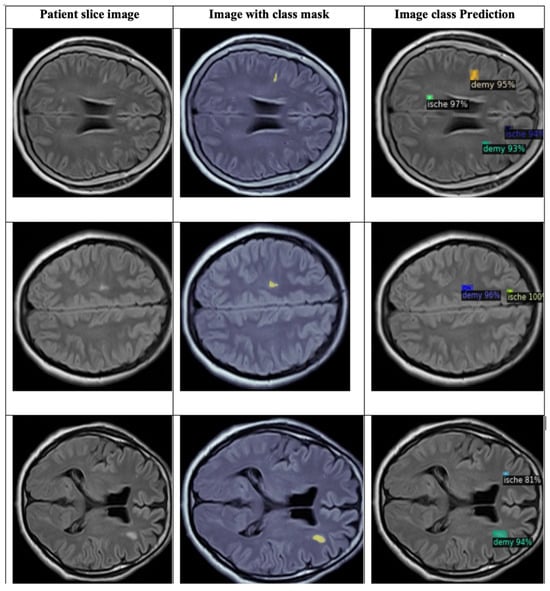

4.2.4. Detectron2 for Detecting WMH Lesions

4.3.2. DETECTRON2 Model for Detection and Classification

- The total loss (‘total_loss’, mean value 0.300) indicates that the model has learned the essential features needed for classification and stabilization with minor fluctuations.

- The box regression loss (‘loss_box_reg’, mean value 0.072) decreases as the model learns to predict better-bounding boxes after stabilizing at a low value. This indicates that the model has become proficient in predicting bounding box coordinates.

- The classification loss (‘loss_cls’, mean value 0.030), through the pass of iteration, decreases and stabilizes, which suggests the model has learned to classify most of the lesions correctly.

- The mask loss (‘loss_mask’, mean value 0.154), shows decreasing and stabilizing values, which indicate a consistent performance in mask predictions.

- The RPN classification loss (‘loss_rpn_cls’, mean value 0.007) indicates a stabilization, which means that the region proposal classification task model has learned to propose regions accurately.

- The RPN localization loss (‘loss_rpn_loc’, mean value 0.029) stabilizes at a low value, which indicates the model’s proficiency with the localizing regions.

- The classification accuracy (‘fast_rcnn/cls_accuracy’ and ‘mask_rcnn/accuracy’) shows improvement through the iterations and gets stabilization values of 0.98 and 0.93 for both accuracies, respectively, which means the model is classifying lesions correctly most of the time (fast_rcnn/cls_accuracy) and that the model has high accuracy in mask prediction (mask_rcnn/accuracy).